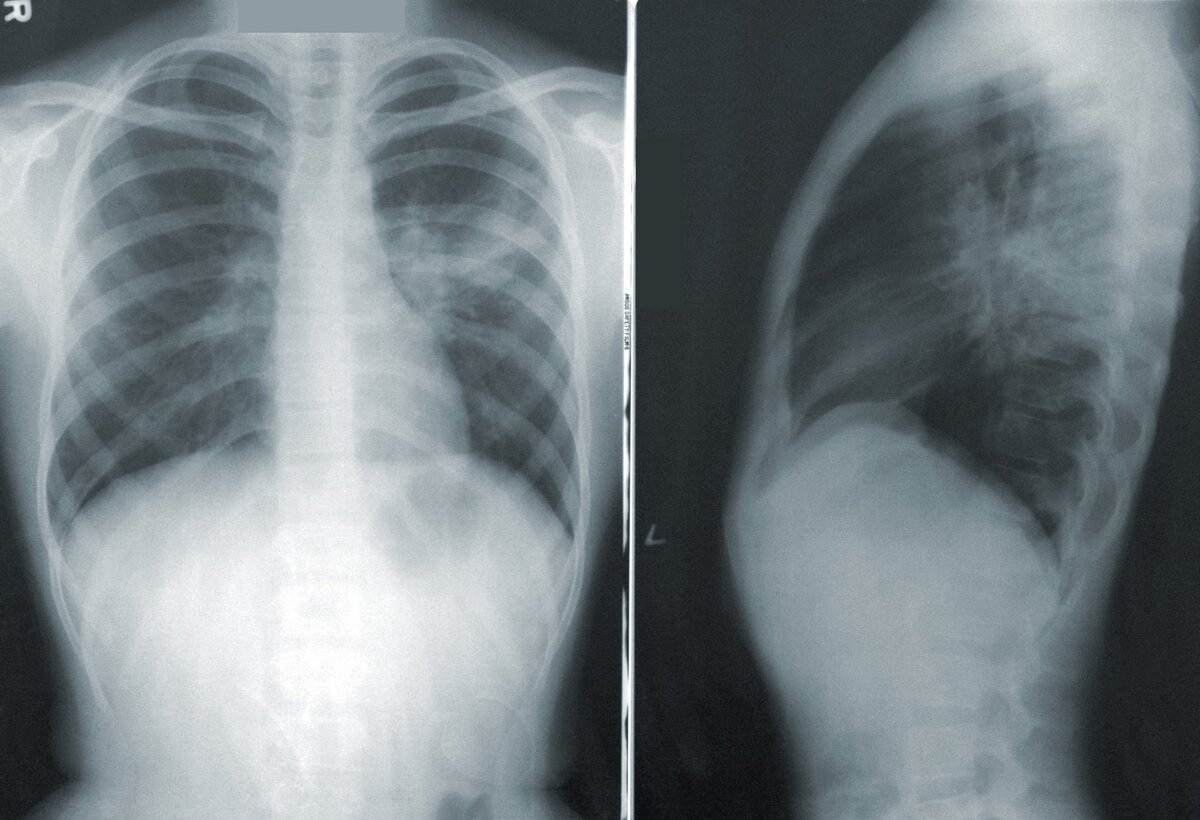

Через пару дней звонок и сообщение: «У вас двусторонняя полисегментарная пневмония ранней стадии. Мы привезём вам лекарства».

Тест оказался отрицательным и картина почти полностью прояснилась: инфекция в бронхах и гортани развивалась очень быстро и буквально за часы успела проникнуть в легкие. Если бы не АБТ, которую я предпринял ранним утром, за полдня масштабы инфицирования стали бы огромными. Не исключено, что сейчас стадия пневмонии была бы более угрожающей.

Лечусь уже пятый день. Ситуация как будто «замерла», почти ничего не меняется: - мокрота исчезла совсем, кашель стал сухим и непродуктивным, температура снизилась до нормальных пределов. Повторная флюорограмма - через 10 дней. Лечение легкой стадии пневмонии, в зависимости от возбудителя - от 7 и до 14 дней.